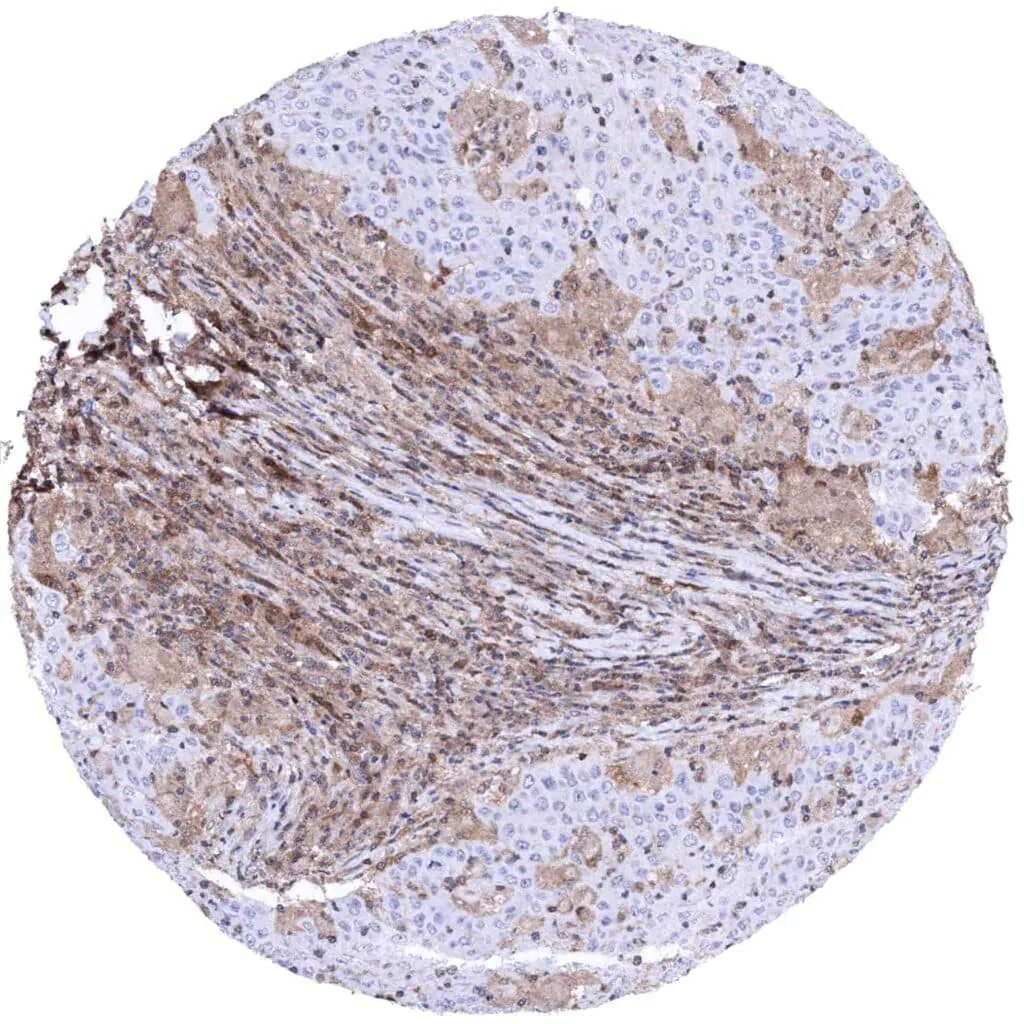

Prostate – Adenocarcinoma (Gleason 4+4=8) with complete absence of MTAP staining in tumor cells. Intense MTAP staining of inflammatory and stromal cells